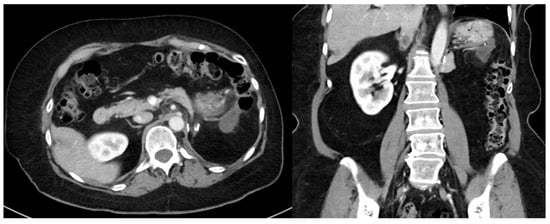

2. Imaging

- High-quality, contrast-enhanced CT imaging of the chest, abdomen, and pelvis should be performed when tumor recurrence is first identified.

- MRI may be useful to help delineate pelvic disease or extent of tumor involvement.